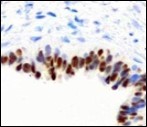

Figure 12.Cutaneous ciliated cyst with nuclear immune reactivity to oestrogen receptors (19).

Epithelium of cutaneous ciliated cyst is immune reactive for pan cytokeratin (CKae1/ae3) antigens, epithelial membrane antigen (EMA), oestrogen receptors (ER), progesterone receptors (PR), Wilm’s tumour protein (WT-1) and paired box gene 8 (PAX8). Immune non reactivity is cogitated for S100, smooth muscle actin (SMA), carcino-embryonic antigen (CEA), desmin, thyroid transcription factor(TTF1), p63 and glial fibrillary acidic protein (GFAP).

Smooth muscle actin (SMA) is immune non reactive, thereby suggesting an absence of smooth muscle within the cyst wall. Intense immune reactivity can be cogitated within epithelial nuclei for oestrogen receptors (ER) and progesterone receptors (PR). Aforesaid immune reactions are indicative of Mullerian origin of cutaneous ciliated cyst.